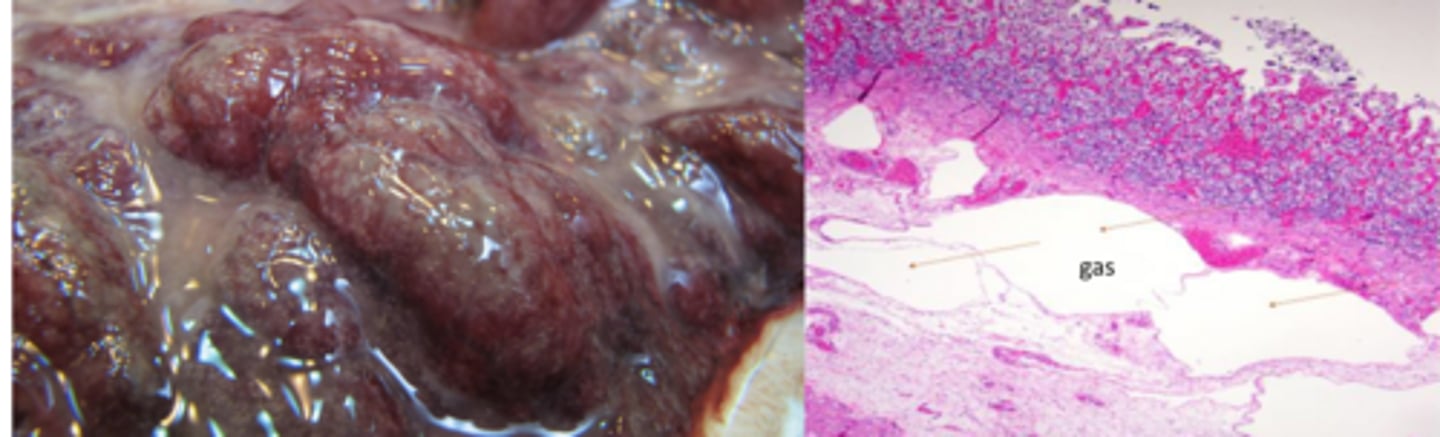

Hemorrhage

Necrosis

Gas bubbles

What lesions will you see in the abomasum of calves affected by C. perferingens or septicum?